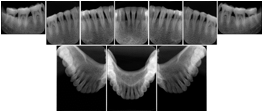

3. A dental provider wishes to capture a series of DICOM IO images for the patient’s dentition. The tooth morphology, teeth are divided into molars, premolars, canines and incisors, and a number of images for each jaw. The anatomic information was captured utilizing the triplet of schema. This standard code sequence is based on ISO 3950-2010, Dentistry - Designation system for teeth and areas of the oral cavity.

Every IO image should have anatomic information either through the primary or modifier sequence.

In most standard cases, images are oriented in structured layouts. These structured displays are useful to be shared between providers for reference purposes.

Table OO.1.1-1 shows structured display standard templates, where Viewset ID is based on the Japanese Society for Oral and Maxillofacial Radiology (JSOMR) classification provided by JIRA (Japan Medical Imaging and Radiological Systems Industries Association, www.jira-net.or.jp). Expected or typical teeth to be imaged location, region and designation codes are based on ISO 3950-2010, Dentistry - Designation system for teeth and areas of the oral cavity. For all the hanging protocols listed in OO.1.1-1, the value to use for Hanging Protocol Creator (0072,0008) is "JSOMR" and the value to use for Hanging Protocol Name (0072,0002) does not include "JSOMR" (e.g., "DL-S001A", not "JSOMR DL-S001A").